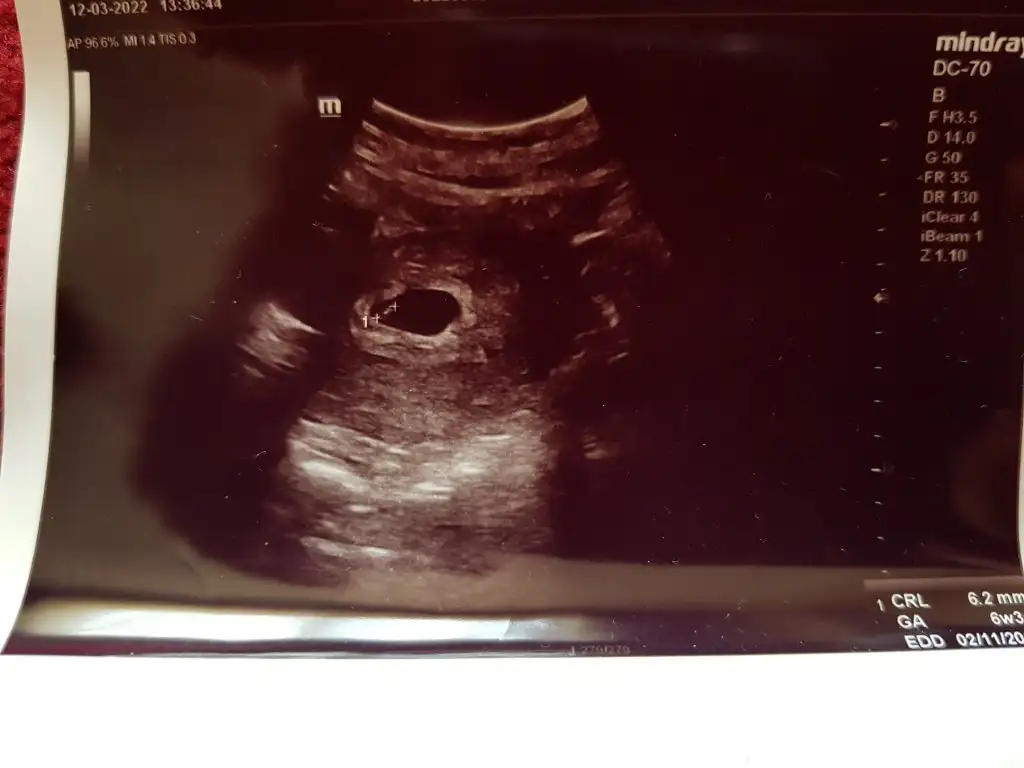

6+2 karından ultrason banada tahminde bulunabilirmisniz

Canim bebeğin erkek miMerhaba 6 haftalık vajinal ultrason tahmin alabilirmiyim

Cinsiyet erkek mi tatlimkarından 6+1 ultrason yorum alabilir miyim ?

Cinsiyet erkek miMerhaba 6 haftalık vajinal ultrason tahmin alabilirmiyim

Emin olmamakla birlikte kiz .şu anda kaç haftaliksinizEki Görüntüle 3066106 6+0 karından